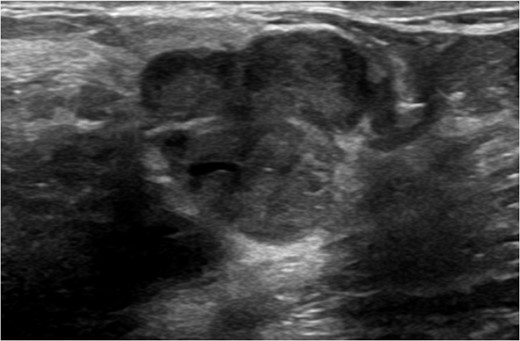

A 56-year-old black female presented to the surgical clinic with a palpable left breast mass that had grown over several months. She denied nipple discharge, breast retraction or family history of malignancy. Physical exam revealed a palpable, subareolar mass without skin changes or asymmetry, and no lymphadenopathy. Her mammogram revealed a 5.4 × 3 cm lesion behind the nipple with Breast Imaging-Reporting and Data System (BI-RADS) 5 classification. An ultrasound indicated a 2.2 × 2 cm lobulated hypoechoic mass with BI-RADS 4 classification (Figs 1–3).

Ultrasound of left breast showing multilobulated lesion BI-RADS 4.

Screening mammogram will identify these lesions as round and well-circumscribed. Ultrasound will show a multilobulated solid mass typically 1–2 cm in size in the retroareolar region. Core needle biopsy under ultrasound guidance is effective for tissue diagnosis [4, 5]. False negatives may occur due to sampling of the capsule instead of the lesion itself.